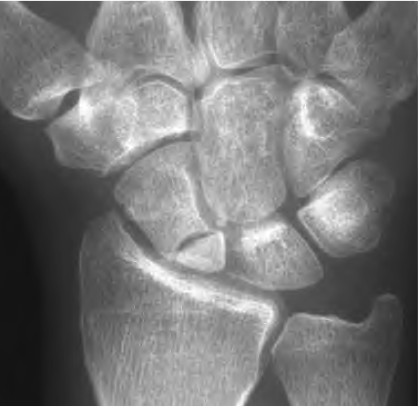

scaphoid with fracture

Published November 19, 2013 at 418 × 407 in Scaphoid Fracture

Scaphoid with proximal pole fracture